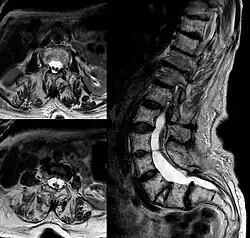

Diastématomyélie

La diastématomyélie est une duplication de la moelle épinière dans le plan sagittal. Un septum osseux ou cartilagineux est volontiers associé à la division médullaire (en son absence on parle de diplomyélie). Ce septum siège habituellement à la face postérieure du corps vertébral et rarement à la face ventrale de l'arc postérieur. Dans la moitié des cas, l'âge de découverte se situe avant 5 ans. Parmi les manifestations cliniques, on retrouve: